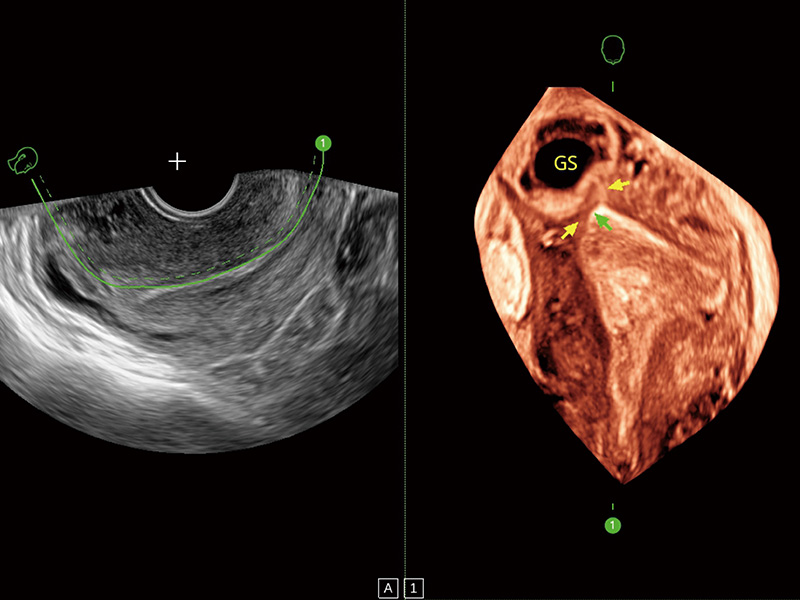

腔内三维成像技术获得显著提升,超大扇角在满足日常基础扫查的同时,支持卵泡自动测量及多种三维渲染模式,为您提供更多的诊断信息,尤其是在子宫畸形的诊断,内膜及肿瘤占位观测中起到了重要的作用。

单角子宫